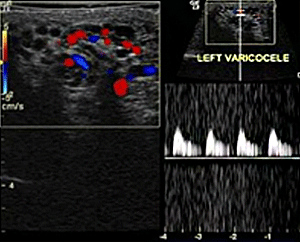

정계정맥류(Varicocele)란?

정계정맥류는 전체 남성 인구의 약 15%에서 발견되고 불임남성에서는 일차적 불임의 경우 35%, 이차적 불임의 경우 75~81%에서 발견되는 흔한 질환고환으로부터 배수되는 망상정맥총(pampiniform venous plexus)이 매우 늘어나 음낭에서 마치 실타래 처럼 만져지는 종물을 말합니다.

정계정맥류의 원인? 정계정맥류가 약 90% 정도 좌측 음낭에 나타나는 이유는 해부학적 구조 때문입니다.

동맥을 통해 고환으로 공급된 혈액은 각각 좌측과 우측의 정맥을 통해 고환을 빠져 나가게 됩니다. 이때 우측 정계정맥은 비스듬하게 굵은 대정맥으로 직접 들어가지만, 좌측 정맥은 직각으로 상대적으로 가느다란 신정맥으로 들어가기 때문입니다. 따라서 우측은 혈관의 길이가 우측보다 길고 저항도 커져 혈액의 역류로 인해 나타나게 됩니다.